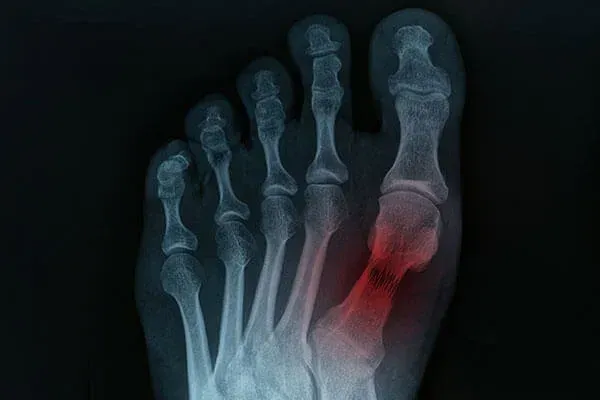

Broken toe bones can either be acute, traumatic fractures, or stress fractures. Traumatic fractures may occur suddenly due to a direct impact—such as stubbing your toe forcefully on a piece of furniture. The affected bone can crack and become displaced. You may hear a sound at the time of injury, feel pain at the point of impact, and see swelling and bruising the following day. You may also have a crooked or abnormal looking toe following the injury. Stress fractures are tiny cracks in bones that occur over time due to repetitive damage, often from playing sports or wearing poorly-fitted shoes. These types of fractures can cause pain during or after normal activity that may go away with rest, pain at the site of the fracture when it is touched, and swelling. Toe fractures that do not receive prompt and proper treatment may become chronically painful, deformed, or arthritic. If you suspect that you may have broken a toe, it is suggested that you see a podiatrist as soon as possible.

Although most people try to avoid foot trauma such as banging, stubbing, or dropping heavy objects on their feet, the unfortunate fact is that it is a common occurrence. Given the fact that toes are positioned in front of the feet, they typically sustain the brunt of such trauma. When trauma occurs to a toe, the result can be a painful break (fracture).

Severe toe fractures may be treated with a splint, cast, and in some cases, minor surgery. Due to its position and the pressure it endures with daily activity, future complications can occur if the big toe is not properly treated.